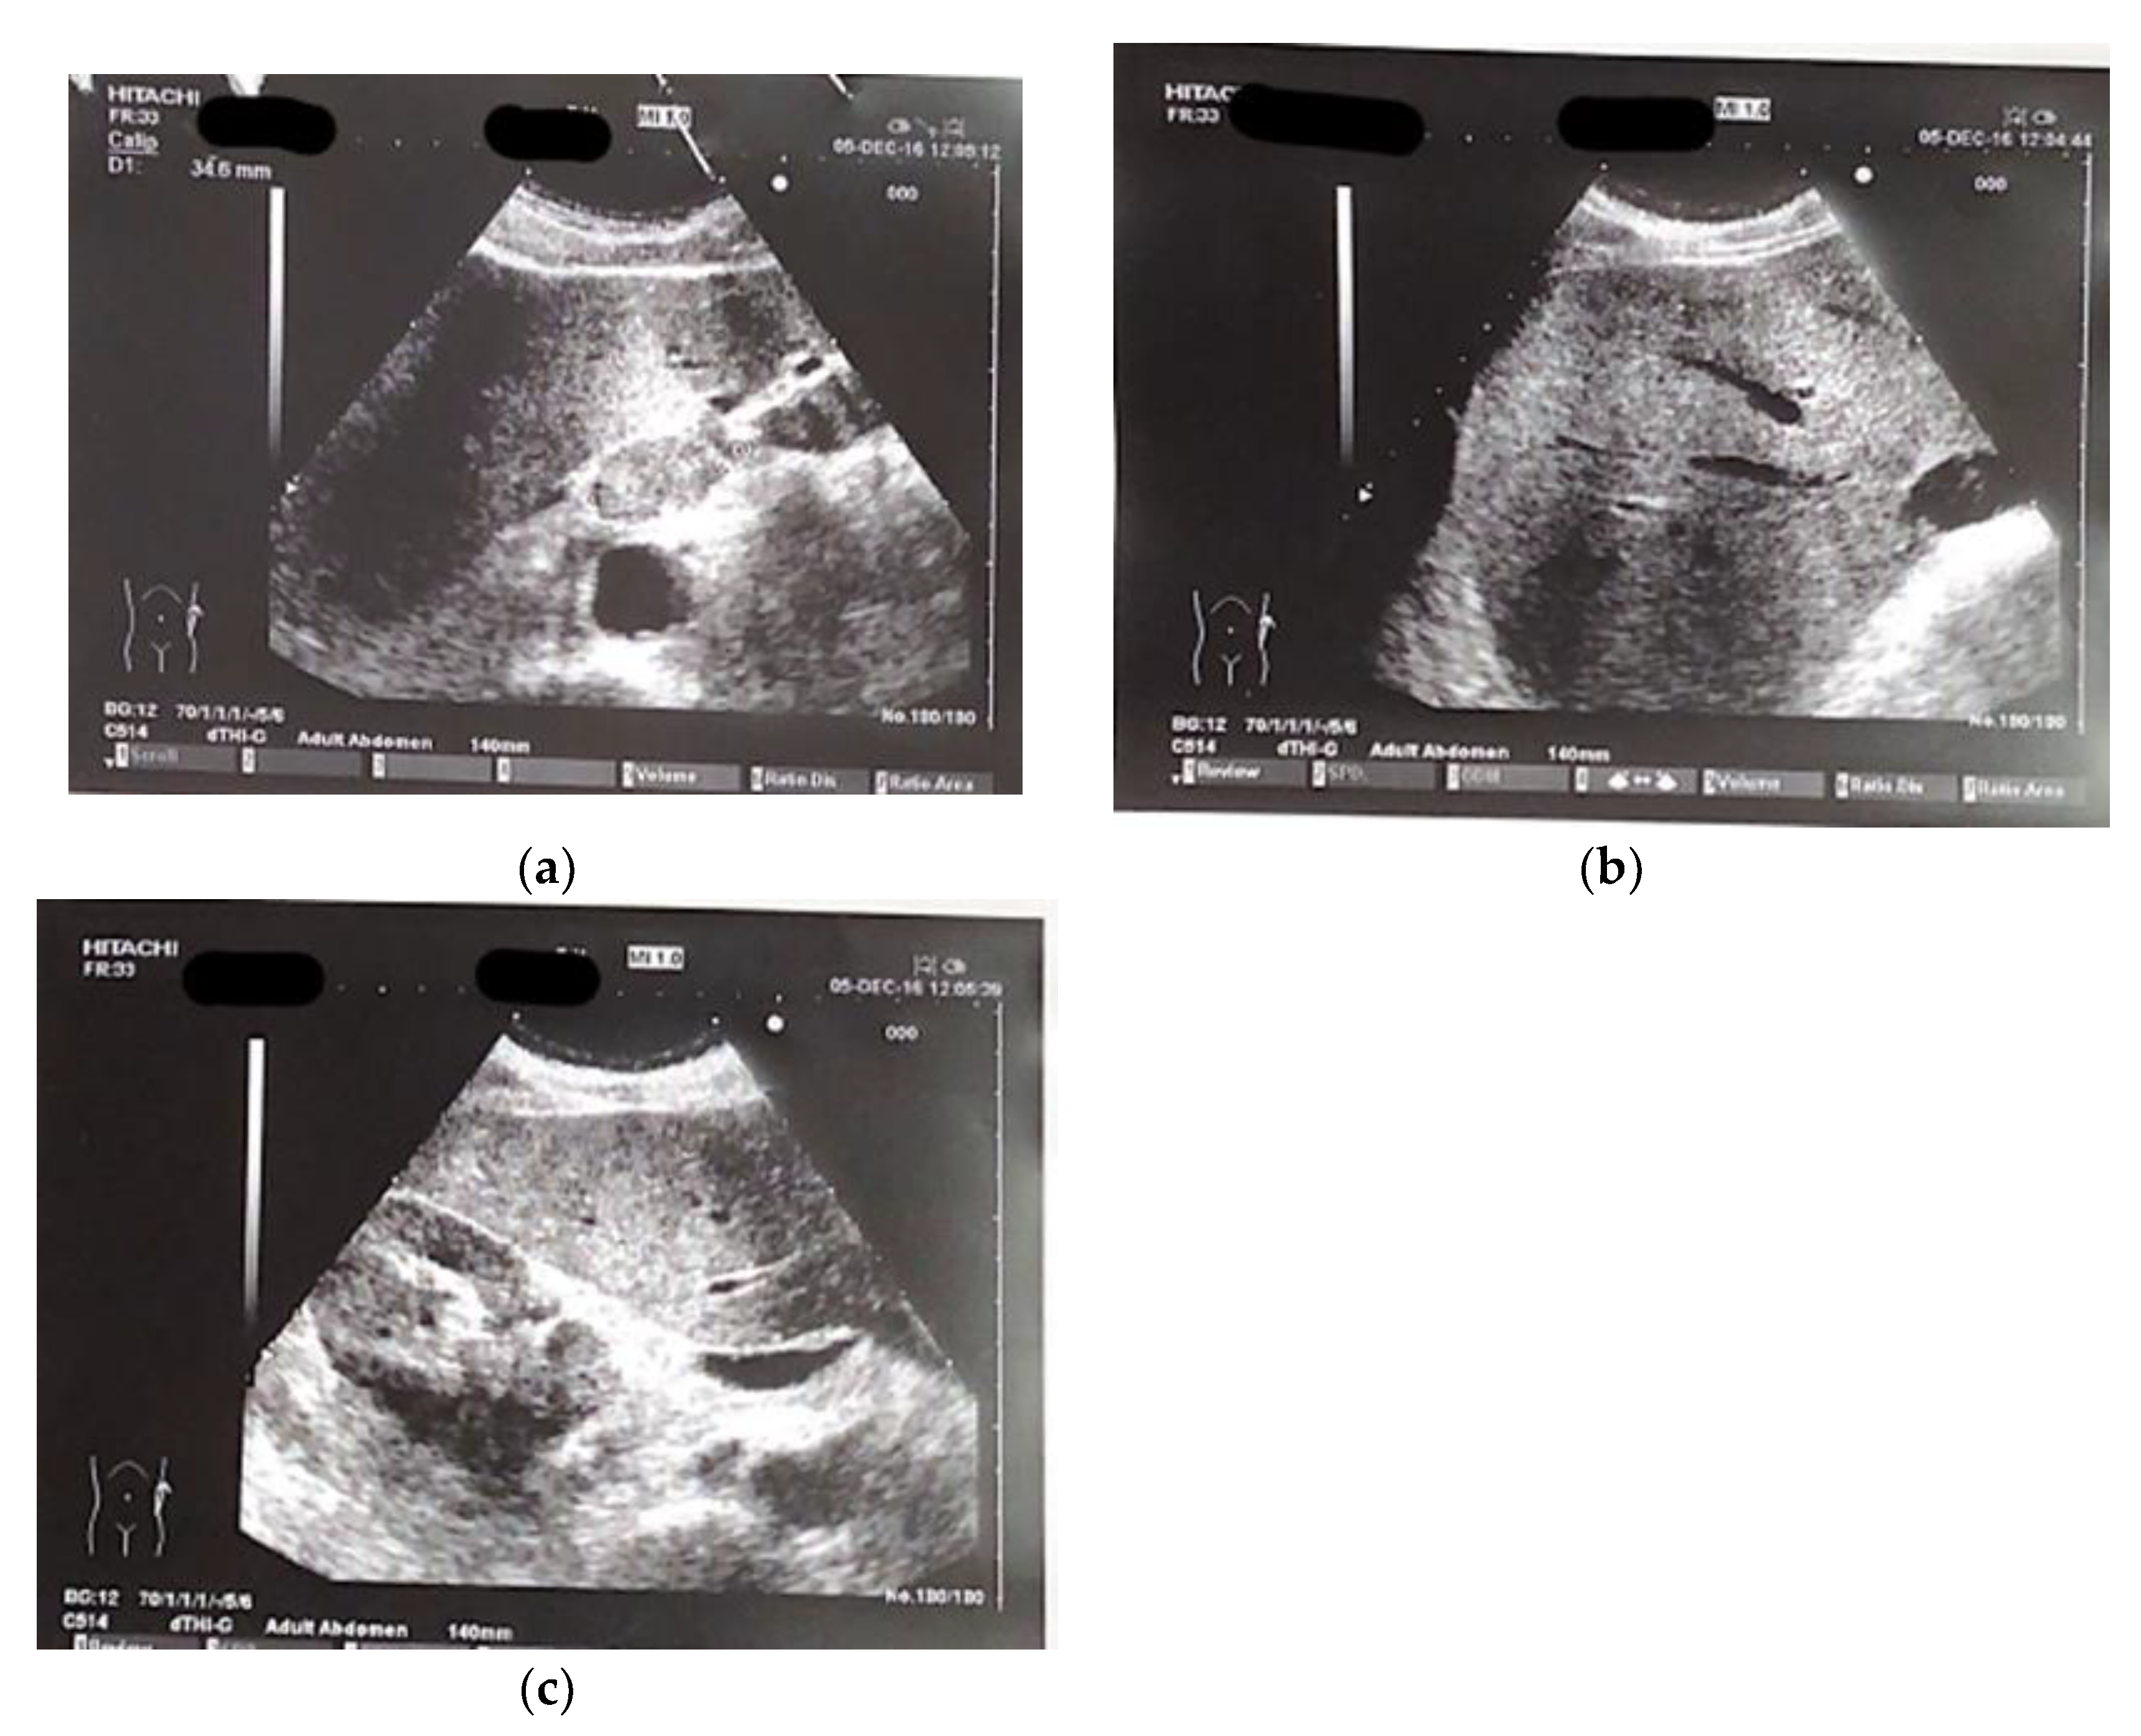

The patient presented at our hospital in 2016 with worsening non-productive night cough, but no dyspnea. He had a history of hypertension and recent diagnosis of gastroesophageal reflux. He was a former smoker, having quit 10 years ago, and had not experienced weight loss in recent months. We performed and abdominal ultrasound which revealed the presence near the hepatic hilum of an area with lobulated contours, roughly oval, displaying iso-hypoechogenic echo structure, with a maximum diameter of 43 mm., suggesting the presence of malignant lymph nodes (fig 1 a-c).

Figure 1. (a–c) Ultrasound images of perihepatic lymphadenopathy.